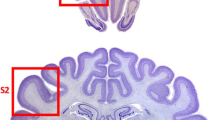

In dogs, as shown in Fig. 5.1, Aβ accumulates in the cortex with a relatively well-described pattern that parallels observations in the human brain (Braak and Braak 1991; Braak et al. 1993; Giaccone et al. 1990; Head et al. 2000; Ishihara et al. 1991; Selkoe et al. 1987; Thal et al. 2002; Wisniewski et al. 1970, 1990). Aβ deposition occurs earliest in the prefrontal cortex of the dog and later in the temporal and occipital cortex (Head et al. 2000), similar to previous reports in humans (Thal et al., 2002). Further, several groups have characterized the age-dependent maturation of Aβ deposits within the canine cortex into several phases (Satou et al. 1997; Schutt et al. 2016). Importantly, the extent of Aβ plaque deposition in the dog brain is linked to the severity of cognitive deficits (Colle et al. 2000; Cummings et al. 1996; Head et al. 1998; Rofina et al. 2006). Interestingly, not all studies show a correlation between Aβ and the presence of canine cognitive dysfunction (CCD) (Chambers et al. 2011; Ozawa et al. 2016). However, studies that show a link between the extent of Aβ and cognition also indicate that the location of the deposition is important. For example, dogs with reversal learning deficits indicative of executive dysfunction tend to show more extensive Aβ deposition in the prefrontal cortex (Cummings et al. 1996; Head et al. 1998). In contrast, poor size discrimination learning ability is associated with large amounts of Aβ in the entorhinal cortex (Head et al. 1998). Soluble Aβ can also be measured in the cerebrospinal fluid (CSF) of dogs, making it a useful marker for aging and cognition intervention studies (Head et al. 2010; Sarasa et al. 2013). The ratio of Aβ42/Aβ40 in the CSF is a good predictor of the extent of Aβ measured biochemically in the brain and also declines linearly with age (Head et al. 2010).

Neuropathology in aging dogs. (a) Aβ immunostaining (6E10 antibody) in the parietal cortex of an aged pet dog (15-year-old Siberian Husky) shows extensive plaque deposition affecting deep cortical layers. (b) CAA (6E10 immunostaining—arrows) in the parietal cortex of an aged dog (14-year-old Sheltie) shows that vascular pathology can be extensive and tends to occur in clusters. Diffuse plaques are also identified by arrowheads. (c) Low-power photograph showing extensive microglial cell labeling (IBA-1 antibody) in gray matter along with intense labeling in the white matter (area below arrows) of a 15-year-old Shih Tzu. (d) Higher magnification photograph from (c) showing that individual microglia contain phagocytic vacuoles and have thickened processes suggesting that some have an activated morphology

Neuroinflammation in the aged human and AD brain may lead to the exacerbation of cognitive decline or potentially mediate other neuropathological events causing dementia (Heneka et al. 2015; Wilcock 2013). Although not as well characterized as neuroinflammation in the human brain, there are several small studies in aged pet dog brains. In a recent study, Schutt and colleagues (Schutt et al. 2016) measured canine cytokines in the prefrontal cortex of 15 aged dogs as compared with 2 young dogs. Pro-inflammatory cytokines were generally at low levels and were not associated with the extent of cognitive dysfunction. However, using measures of glial activation (microglial cells and astrocytes), increasing numbers of both types of cells were associated with more extensive CCD in a study of 37 dogs with various breeds included (Ozawa et al. 2016). Similarly, the level of S100β astrocytosis, a putative measure of inflammation, is also correlated with cognitive deficits in pet dogs (Pugliese et al. 2006).